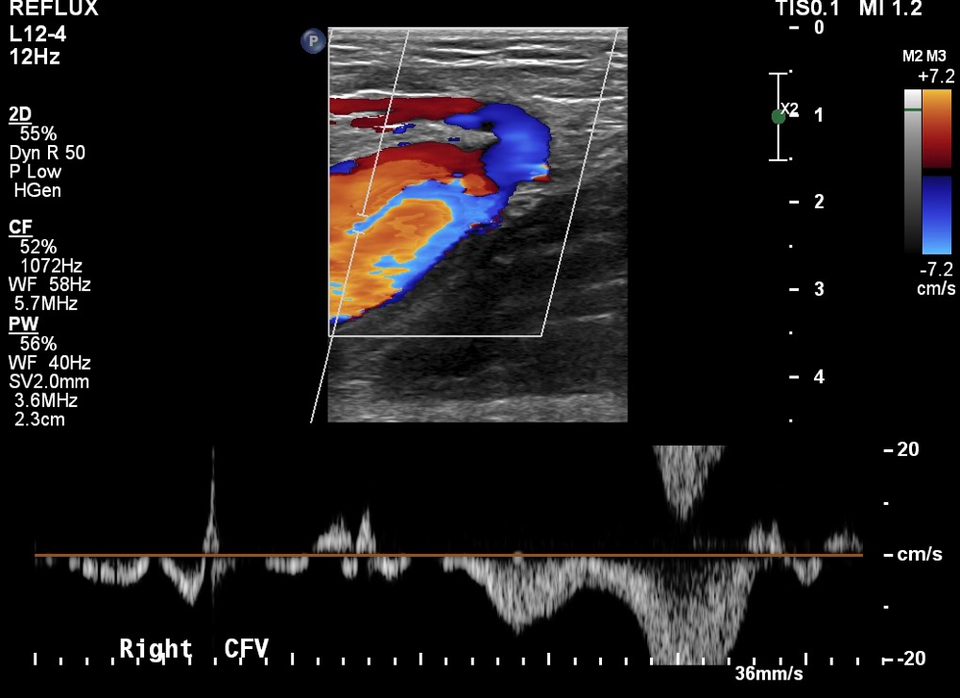

Varicose Veins of the Lower Extremity Doppler US Evaluation Protocols Gold Standard Test For Varicose Veins Turning now to pvr, the gold standard investigation has been shown to be the transvaginal venous duplex ultrasound scan. Randomized clinical trial comparing endovenous laser ablation with surgery for the treatment of primary great saphenous varicose. Phlebography by vein x‑ray using contrast medium was the gold standard for vein diagnosis by imaging for decades. Duplex ultrasound scanning is now the. Gold Standard Test For Varicose Veins.

Figure 1 from Vascular Ultrasound Exam for Varicose Veins . Importance Gold Standard Test For Varicose Veins Randomized clinical trial comparing endovenous laser ablation with surgery for the treatment of primary great saphenous varicose. While open surgery remains the ‘gold standard’, most veins can be treated successfully with a range of options. Phlebography by vein x‑ray using contrast medium was the gold standard for vein diagnosis by imaging for decades. Turning now to pvr, the gold standard. Gold Standard Test For Varicose Veins.